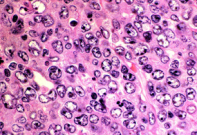

| + | לימפומה של תאי B גדולים - Large b cell lymphoma | ||